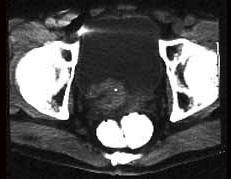

膀胱癌的恶性程度取决于 ( )A、血尿的程度B、患者年龄C、肿瘤的大小和数目D、治疗方法E、浸润膀胱癌的深度及组织学等级

问题 膀胱癌的恶性程度取决于 ( )

选项 A、血尿的程度 B、患者年龄 C、肿瘤的大小和数目 D、治疗方法 E、浸润膀胱癌的深度及组织学等级

答案 E